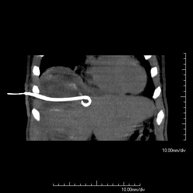

Consisteix en obtenir una mostra de teixit d'una determinada lesió localitzada a la cavitat abdominal. En ocasions es realitza sota sedació, amb l'ajuda de l'equip d'anestèsia. S'utilitzen agulles que permeten l'obtenció d'un cilindre de la lesió que s'ha d'estudiar, que s'enviarà a Anatomia Patològica per a la seva anàlisi histològica. Tot el procediment es realitza controlat per imatges obtingudes per Tomografia Computaritzada (TC) en diversos moments de la biòpsia mitjançant l'ús de Fluoroscòpia –TC. Després de la prova, el pacient resta hospitalitzat per controlar la seva evolució. És necessari que portin proves de coagulació abans de la punció. - Drenatge abdominal guiat per TC (abscessos, col·leccions)

Consisteix en col·locar un catèter de drenatge sobre una col·lecció líquida localitzada a la cavitat abdominal, amb la intenció de buidar el màxim possible aquesta col·lecció. El pacient ha de mantenir el drenatge alguns dies, normalment fins que no sigui productiu. Sovint es realitza sota sedació, amb l'ajuda de l'equip d'anestèsia. Tot el procediment es realitza controlat per imatges obtingudes per Tomografia Computaritzada (TC) en diversos moments de la prova mitjançant l'ús de Fluoroscòpia –TC. Després de la prova, el pacient resta hospitalitzat. És necessari que porti les proves de coagulació abans de la prova.

Consisteix en obtenir una mostra de teixit d'una determinada lesió determinada de lesió localitzada en la cavitat abdominal. A vegades es realitza sota sedació, amb l'ajuda de l'equip d'anestèsia. S'utilitzen agulles que permeten l'obtenció d'un cilindre de la lesió que s'ha d'estudiar, que s'enviarà a Anatomia Patològica per a la seva anàlisi histològica. Tot el procediment es realitza controlat per imatges obtingudes per Tomografia Computaritzada (TC) en diversos moments de la biòpsia mitjançant l'ús de Fluoroscòpia-TC. Després de la prova, el pacient resta hospitalitzat per controlar la seva evolució. És necessari que porti proves de coagulació abans de la punció. - CT-guided abdominal drainage

It consists of placing a drainage catheter over a collection of fluid located in the abdominal cavity, with the intention of emptying as much of the collection as possible. The patient should keep the drain in place for a few days, usually until it is no longer productive. It is often performed under sedation with the help of an anaesthesia team. The entire procedure is monitored using images obtained by computed tomography (CT) at various stages of the test, using CT fluoroscopy. After the test, the patient remains hospitalised. Coagulation tests must be performed before the test.